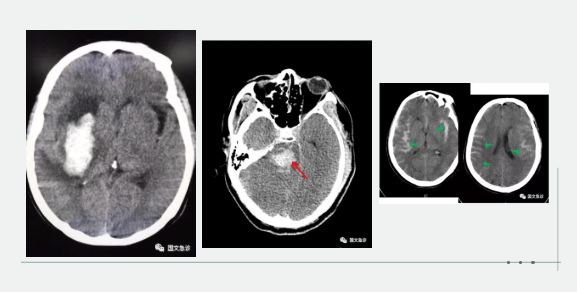

突發(fā)意識不清兩小時入院。據(jù)家屬描述“發(fā)現(xiàn)的時候老爺子躺在地上叫了好幾聲也沒有反應(yīng),上去推了推也沒動靜趕忙就打120了。根據(jù)該家屬的描述,緊急為患者進(jìn)行查體:該患者意識成昏迷狀態(tài),查體不合作,雙側(cè)瞳孔等大等圓,呼吸間斷 血壓237/115mmhg。內(nèi)科醫(yī)生進(jìn)一步向家屬了解患者既往血壓情況,該家屬表示:“血壓一直都很高,降壓藥也不按時吃就難受的時候吃一片”。進(jìn)一步考慮患者腦內(nèi)出血,立即行頭部CT。為患者打開急診綠色通道“遵循檢查或繳費的原則”。CT結(jié)果顯示患者左側(cè)大腦半球出血、小腦出血、腦室積血。醫(yī)生立即向家屬交代病情,該家屬哽咽著說:“你說這早上剛還一起吃團(tuán)圓飯呢,一轉(zhuǎn)身的工夫,老爺子就倒地不起了。醫(yī)生您說啊,好好的一個人怎么就腦出血了?以前除了血壓高一點癥狀都沒有呀!”

突發(fā)意識不清,1小時入院。該妻子滿眼淚水地向醫(yī)生訴說:“我們剛吃完飯,他說困了睡一會兒,這怎么突然就叫不醒了呢?醫(yī)生您快看看,這是咋了呀?”“李先生平時身體怎么樣?”“我家老李平時身體可好了,你別看他長得胖,一年感冒的次數(shù)都少。對了,就是血壓有點高。”根據(jù)家屬描述,立即為患者查體:該患者呈深度昏迷狀態(tài),雙側(cè)瞳孔不等大 左側(cè)3.5mm、右側(cè)5.0mm,血壓250/190,雙側(cè)病理征陽性。初步考慮患者腦內(nèi)出血,急行頭部CT檢查。結(jié)果示:右側(cè)小腦及腦干不規(guī)則高密度灶破入腦室,三腦室及四腦室內(nèi)見高密度灶?;颊卟∏槲V蒯t(yī)生立即為患者辦理入院,急忙送往ICU(重癥監(jiān)護(hù)室)進(jìn)行進(jìn)一步治療。